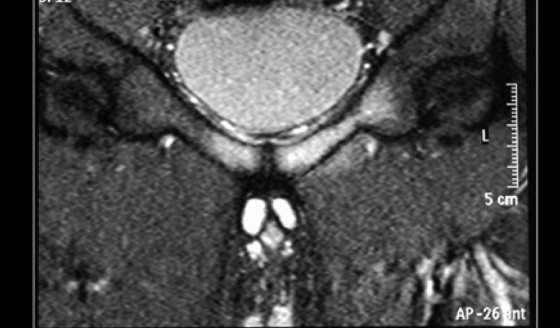

#InfografíaMSP   Los sueros intravenosos son fundamentales en el manejo de pacientes hospitalizados: permiten mantener la hidratación, reponer electrolitos y administrar medicamentos o nutrientes esenciales.

En esta infografía te explicamos las principales indicaciones clínicas, los tipos de soluciones más utilizadas y cómo se distribuyen en el organismo según su composición.